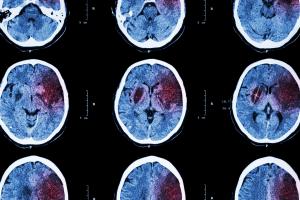

Ici, les chercheurs examinent les scanners cérébraux de 87 adolescents et adultes atteints de TOC modéré à sévère répartis au hasard à suivre, durant 12 semaines, l'une des 2 thérapies. L’expérience montre qu'en général, les deux permettent une réduction les symptômes et que pour la majorité des participants, la thérapie d'exposition, une forme de thérapie cognitivo-comportementale (TCC) est plus efficace que la thérapie de gestion du stress (SMT : stress-management therapy).

Cependant l’analyse des scintigraphies cérébrales prises avant et après le traitement apporte des résultats frappants : ces images ont été prises pendant que les patients effectuaient une tâche cognitive simple et recevaient une petite récompense monétaire si la tâche était correctement accomplie.

Quelles sont les zones cérébrales clés ? Ce sont en fait les mêmes que celles déjà documentées comme impliquées dans le développement des TOC et préconisées pour la stimulation magnétique transcrânienne-une autre thérapie « émergente » pour les TOC. Ces zones impliquent le réseau cingulo-operculaire pendant la tâche cognitive et le réseau orbitostriato-thalamique lors de la récompense.